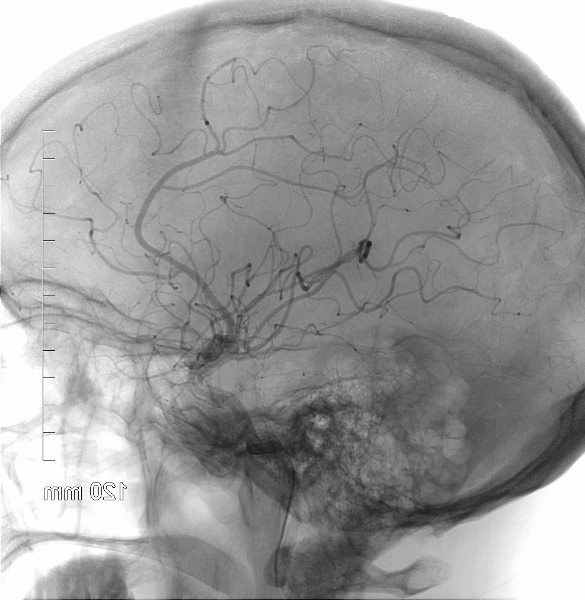

Early Friday morning, I was visited by a doctor who turned out to be my primary neurologist, from Interventional Radiology, a department I had never heard of before; this was one of the first of many new terms I was going to be learning over the course of my stay. He explained that they’d found a small (about 3mm) aneurysm at the main branch of my right internal carotid artery, which had ruptured the previous morning. “It’s a good thing it stopped bleeding on its own,” he told me, “or we wouldn’t be having this conversation.”

The surgeon’s plan was to perform a coil embolization procedure—something else I had never heard of, and to which my immediate reaction was, wait, aren’t embolisms bad?—by going in through my femoral artery, up to my brain, and inserting a small coil of platinum into the aneurysm. This would stop up blood flow to the aneurysm, clot, and eventually cause the aneuyrsm to collapse. A litany of possible side effects and complications was presented, none of which sounded worse than what had already happened and what was likely to happen if we did nothing, so I agreed to the procedure and it was scheduled to occur several hours later. (I’ve since learned that a cerebral aneurysm that ruptures once is almost certain to rupture again within a few days to a few weeks, and that the second rupture is usually much worse. This explains the hurry to get the surgery done: There was a clock, and it was ticking.)

When the time came for surgery my bed was rolled out to the Interventional Radiology operating theatre, which consisted of all kinds of fancy equipment on tracks in the ceiling that could be moved every which-way, and a giant monitor (bigger than the TV in our house) with my name displayed on it and a brain scan which I assumed was mine. I felt like I had been transferred to the sick bay on the Enterprise. After everything was ready I was moved to the operating table, where I was introduced to my anesthesiologist, answered a few questions, and then woke up in recovery. Once I was stable enough to be moved (I later learned that I’d had a pretty rough time of it coming out of anesthesia, with signs of atrial fibrillation and tachycardia and some other terms I didn’t catch; I don’t remember any of that), they wheeled me back to my room in ICU, where several friends were waiting for me. Back in ICU, I developed a serious case of the full-body shakes, which was also related to the anesthesia. I was given intravenous Demerol to try to alleviate the shaking, but it made me incredibly nauseated within seconds. This is all a little fuzzy in my memory but I’m told that I pushed myself upright and pointed and said: